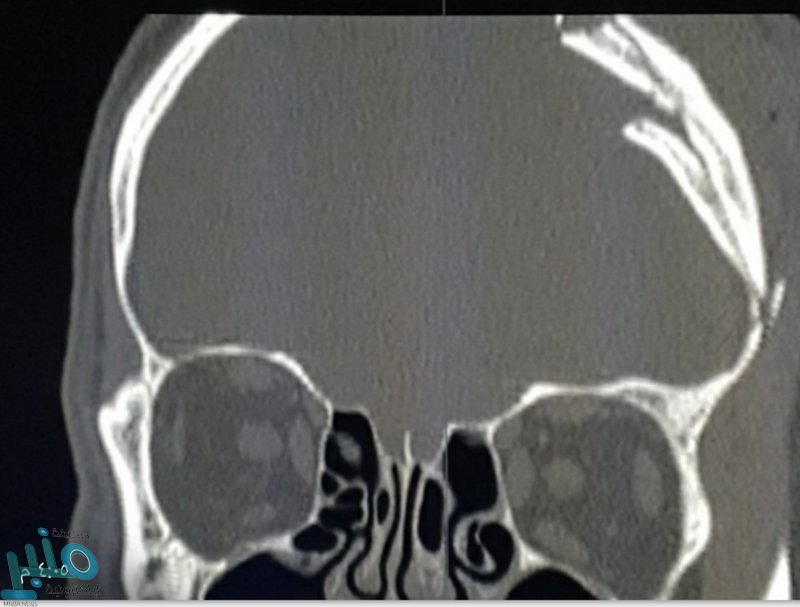

أجرى فريق طبي مختص في مستشفى جنوب القنفذة العام جراحة متقدمة وناجحة ولله الحمد لمصاب في الجمجمة بسبب سقوطه من سقالة تجاوز ارتفاعها العشرة أمتار نتج عنه كسر مضاعف مفتوح في الجمجمة ونزيف خارج الأم الجافية وكذلك قطع للأم الجافية مع تسرب للسائل النخاعي.

وأكد متحدث صحة القنفذة إبراهيم محمد المتحمي لـ”سبق” أنه قد اُجريت للمصاب عملية جراحية في اليوم نفسه من دخوله للمستشفى لرفع العظم المنخسف وتفريغ النزيف خارج الأم الجافية، وإصلاح قطع الأم الجافية وإيقاف تدفق السائل النخاعي، حيث تكللت العملية بحمد الله بالنجاح وتم إعادة شكل الجمجمة إلى وضعها الطبيعي قبل الجراحة.